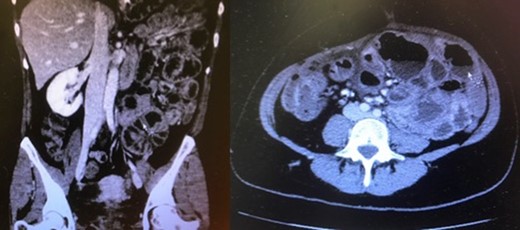

The patient was lastly readmitted for abdominal distension, vomiting and obstipation. Bowel obstruction was suspected. A computed tomography (CT) of the abdomen and pelvis with intravenous contrast injection was performed. It showed dilated small-bowel in the left flank with non-distended distal bowel loops (Fig. 1), consistent with an asymmetrical abdomen that was more distended on the left side. No obvious transition point could be objectified. The clinical presentation and imaging were suggestive of SBO. After several days of unsuccessful conservative management with a nasogastric tube and intravenous hydration, she was taken to the operating room where an exploratory laparotomy revealed a hick adherent fibrous sheath that was encapsulating most of the small bowel (Fig. 2). Extensive adhesiolysis and laborious excision of the capsule were performed and ‘Seprafilm’, an adhesion barrier, was applied [2]. A severely stenotic 10 cm bowel segment was resected and reanastomosed. The postoperative period was complicated with pulmonary embolism, ileus and ascites. Nonetheless, she recovered well and was eventually discharged.

Distended small-bowel loops located mainly in the left hemiabdomen.